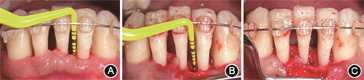

像(4)下前牙牙周手术治疗:在正畸排齐压低下前牙后,于正畸治疗后17个月行牙周植骨术联合GTR,翻瓣后可见31、32间存在4 mm骨内缺损,刮净肉芽组织后植入骨粉(Bio-Oss,Geistlich,瑞士),并覆盖可吸收胶原膜(Bio-Gide,Geistlich,瑞士),缝合(图9)。结合术前根尖片及术中口内像可见正畸压入后,31、32间牙槽骨吸收类型由水平型吸收转为垂直型吸收,有利于牙周再生术的成功实施,术后根尖片进一步显示骨充填良好(图10)。

本例患者下前牙牙槽骨呈水平型吸收,由于水平型骨吸收区域无法创造充足且稳定的再生空间,通常认为此类骨缺损并非牙周再生性手术的最佳适应证[11]。动物研究显示,正畸治疗可改善大鼠牙髓、牙周膜及牙槽骨中的血液循环[12]。正畸压低还可将患牙牙槽骨缺损类型由水平型吸收转变为垂直型吸收,Cao等[13]对56颗存在水平型骨缺损的伸长前牙采用正畸压低联合牙槽嵴上纤维环切术治疗,有14颗患牙骨缺损类型转变为垂直型吸收。本病例通过正畸治疗排齐牙列并压低下前牙,成功形成4 mm的骨内缺损,创造了足够的再生空间,随后进行牙周再生性手术并取得良好效果,为牙槽骨水平型吸收患牙的牙周再生治疗提供了参考。